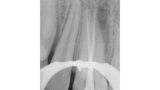

Endodontické ošetření horního středního řezáku s atypickou anatomií